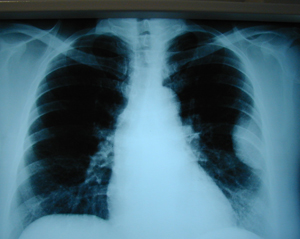

Εικόνα 1

Ακτινογραφία θώρακος (οπισθιοπροσθία λήψη) που δείχνει σκίαση στον αριστερό κάτω λοβό.